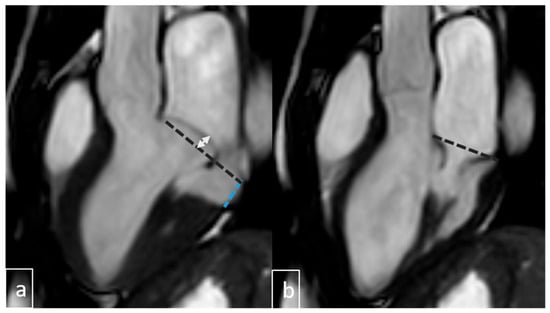

2.4. Image Analysis

3.6. Cardiac MRI Findings in MAD